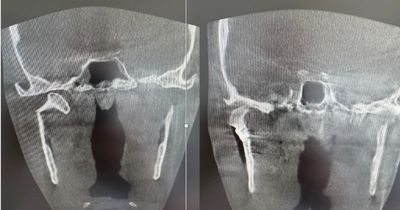

Left image: before surgery – the broken condyle is tilted and out of place.

Right image: after surgery – the bone is straight, solidly fixed, and the joint position is restored.